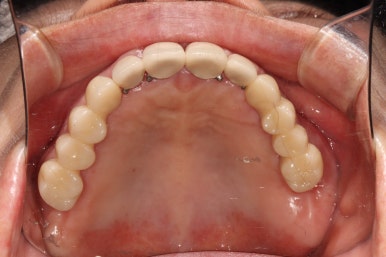

그렇게 완성된 최종 보철물 형태입니다.

임시치아와 다르게 지르코니아 크라운으로 제작되어 훨씬 단단하고 매끈하고 이상적인 형태를 가진걸 보실 수 있으실거에요.

위 아래 앞니 모두 적절한 길이로 회복이 되었고, 어금니도 이상적인 형태를 보여주고 있습니다.

식사 시 음식이 덜 끼도록 치아와 치아사이를 최대한 닫아놓은 모양입니다.

위아래 모두 아주 이상적인 형태로 제작된 치아모양의 지르코니아 크라운을 보실 수 있을거에요.

이 정도면 전체 구강 재건 (full arch rehabilitation)이라고 불러야 합니다.